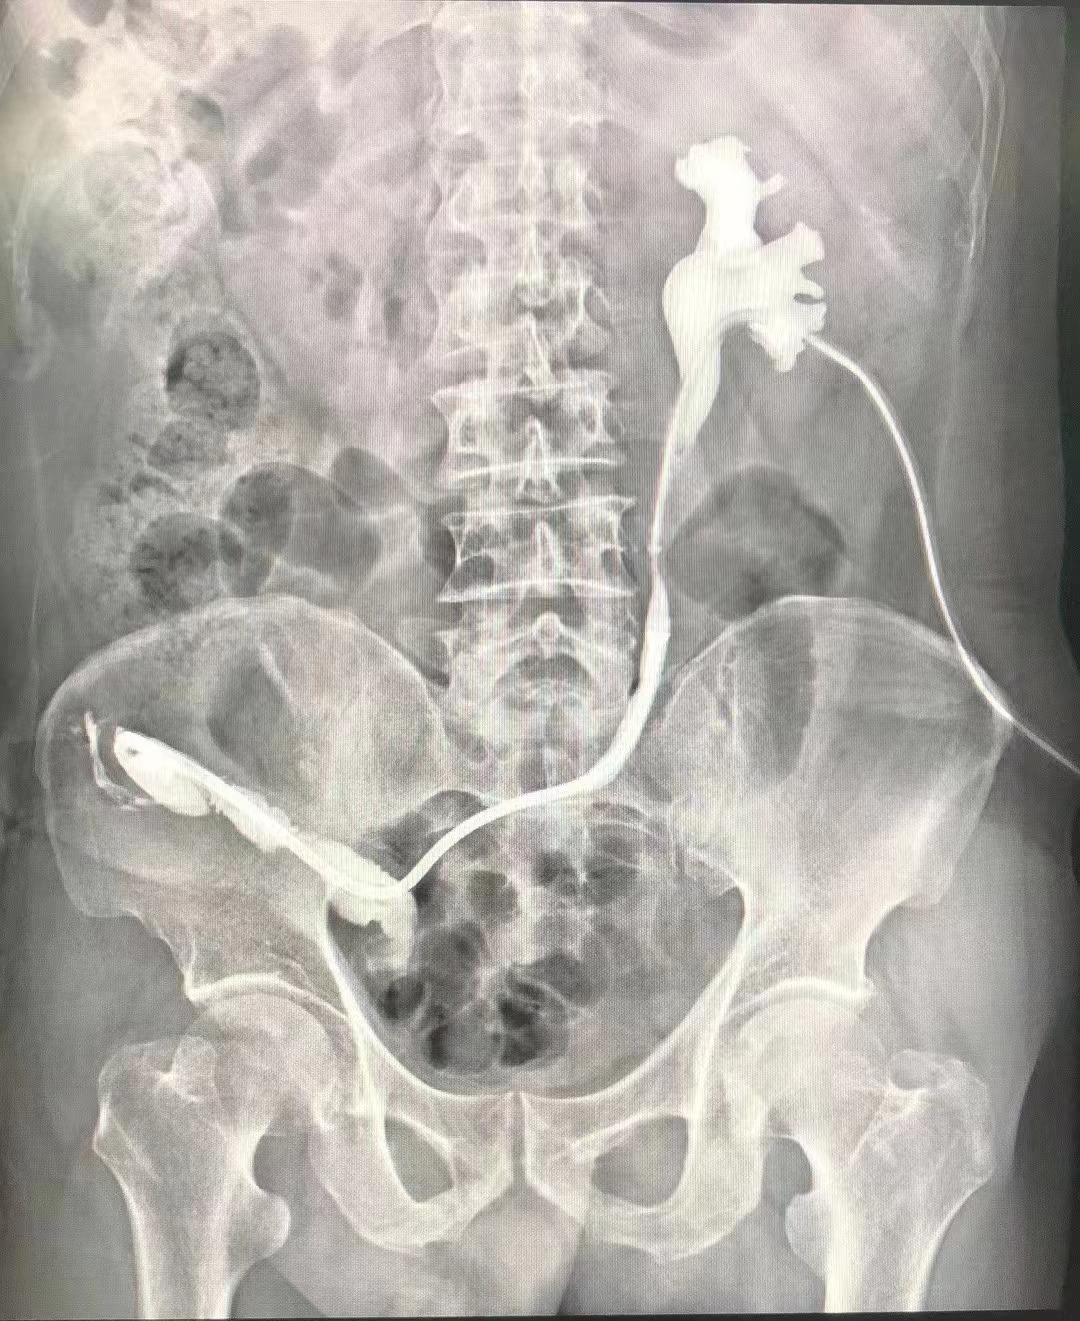

2023年8月31日,武汉同济航天城医院曾晓勇院长带领泌尿外科团队完成了全国首例温控记忆合金输尿管支架治疗输尿管-回肠吻合口狭窄。此次创新手术利用国际最前沿的温控记忆合金输尿管支架技术,结合输尿管软镜技术,为一名膀胱癌尿流改道术后的患者成功解除了输尿管-回肠吻合口狭窄,为患者解决了困扰多年的肾造瘘问题,使其重新恢复到较满意的生活状态。这是国内首次运用这项技术开展此类高度复杂的手术,标志着武汉同济航天城医院泌尿外科微创技术应用取得了重要突破,为国内众多膀胱癌尿流改道输尿管-回肠吻合口狭窄这类患者提供了全新微创解决方案。

为尽早解除患者病痛,在完善术前检查后,我院泌尿外科团队进行术前讨论,根据患者的身体条件制定最佳手术方式,经科室讨论决定行温控记忆合金输尿管支架治疗输尿管-回肠吻合口狭窄。手术由曾晓勇院长主刀实施,在麻醉科和手术室的密切配合下手术十分成功,目前患者恢复良好,于9月6日顺利出院。